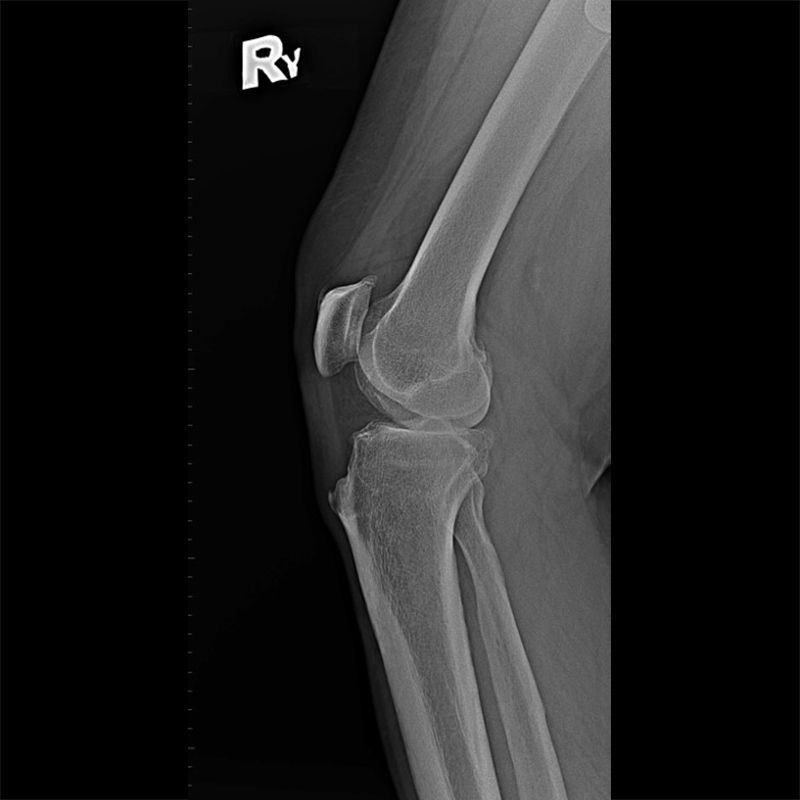

機器手臂手術 首頁 案例分享 膝關節手術 機器手臂手術 蔡女士 78歲 術前 術後 陳女士 70歲 術前 術後 術前 術後 ANGEVINE女士 73歲 術前 術後 U.S.A Mark 73歲 術前 術後 藍女士 78歲 術前 術後